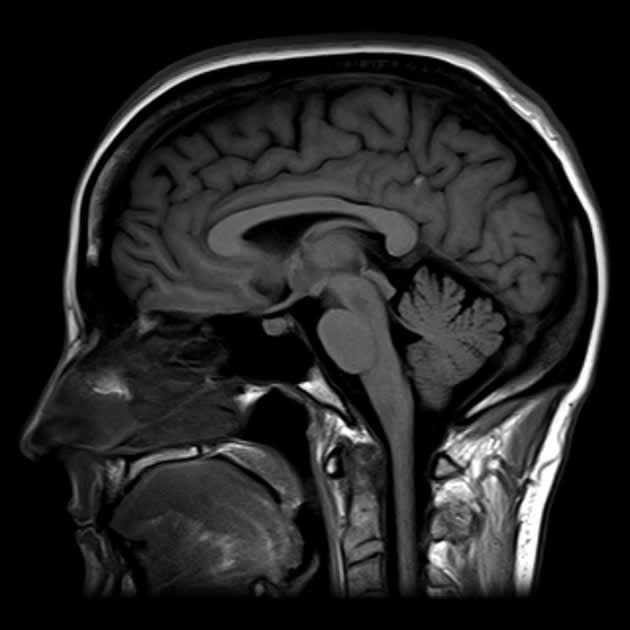

Source: skcusagyl.pages.dev How to Interpret Brain MRIs 3 Essential Techniques , MRI for General Practitioners - person under the age of 16 MRI for General Practitioners - person 16 years or older MRI - specialists Mammography OPG Pregnancy & nuchal translucency ultrasound Shoulder & knee ultrasound Referral guidelines for allied health Please note you are free to select the physio of your choice providing they are registered to provide services under.